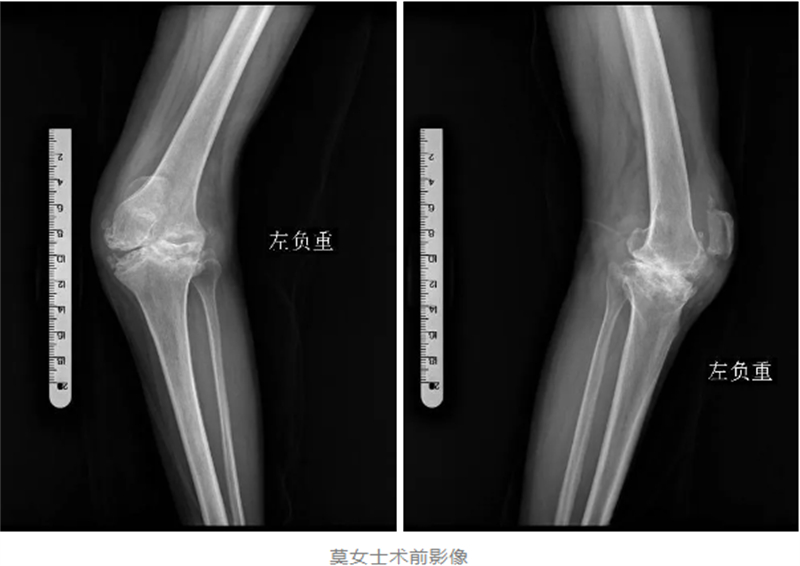

入院后,經過詳細的檢查,醫生發現莫女士的左膝關節已經嚴重破壞,甚至達到了毀損的程度。韋健博士介紹,對于常規的“腿不歪”的嚴重膝關節磨損,用普通膝關節假體進行人工膝關節表面置換手術即可解決行走及疼痛問題,但對于莫女士這種罕見的、嚴重變形的毀損型膝關節,普通膝關節假體已經無法滿足手術需求。

對于莫女士來說,這不僅是一次手術,更是她重獲健康、重拾生活信心的關鍵。因此,韋健博士及其團隊經過充分的討論和周密的術前準備,決定采用髁限制型人工膝關節假體,為莫女士進行一場“美容”手術,幫助她實現重塑“大長腿”的夢想。